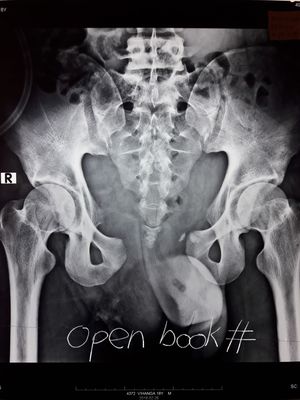

Pelvic fracture is a disruption of the bony structure of the pelvis, including the hip bone, sacrum and coccyx. The most common cause in the elderly is a fall, but the most significant fractures involve high-energy forces, as from a motor vehicle crash, cycling accident, or fall from significant height. Pregnancy or childbirth can cause mild to complete disruption/instability of the pelvic joints symphysis pubis, sacroiliac joint. Diagnosis is made on the basis of history, clinical features and special investigations usually including X-ray and CT. Because the pelvis cradles so many internal organs, pelvic fractures may produce significant internal bleeding which is invisible to the eye. Emergency treatment consists of advanced trauma life supportmanagement. After stabilisation, the pelvis may be surgically reconstructed.